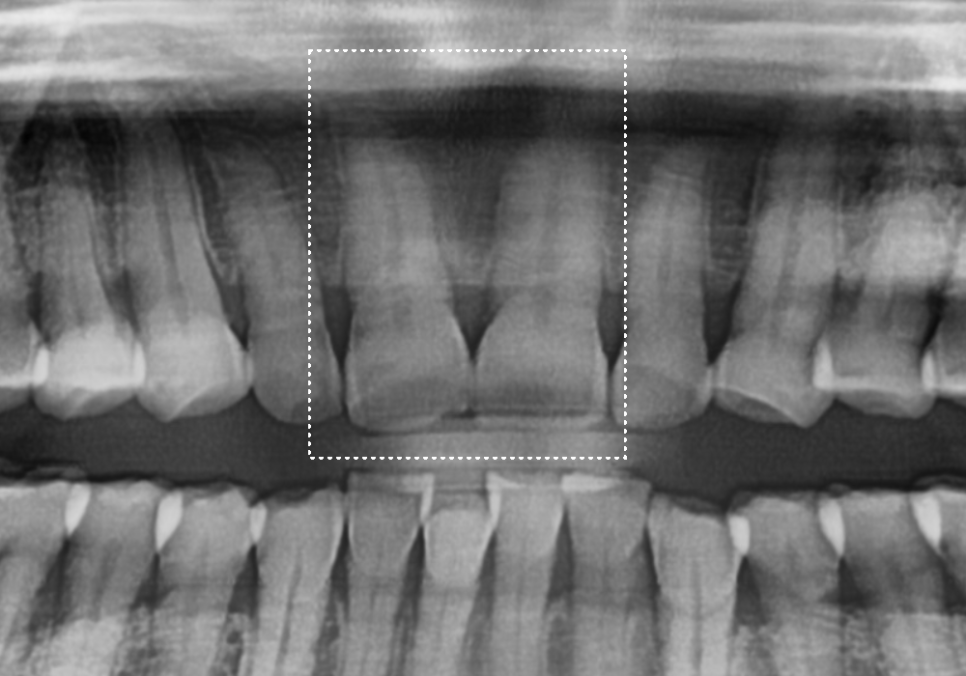

다행히 앞니(#11, 21)를

정밀하게 살펴본 결과

금이 치아 겉면에만

머물러 있는 상태였습니다.

신경이라는 예민한 통로까지는

손상되지 않아 신경치료 없이

크라운 치료로 진행하기로 했는데요.